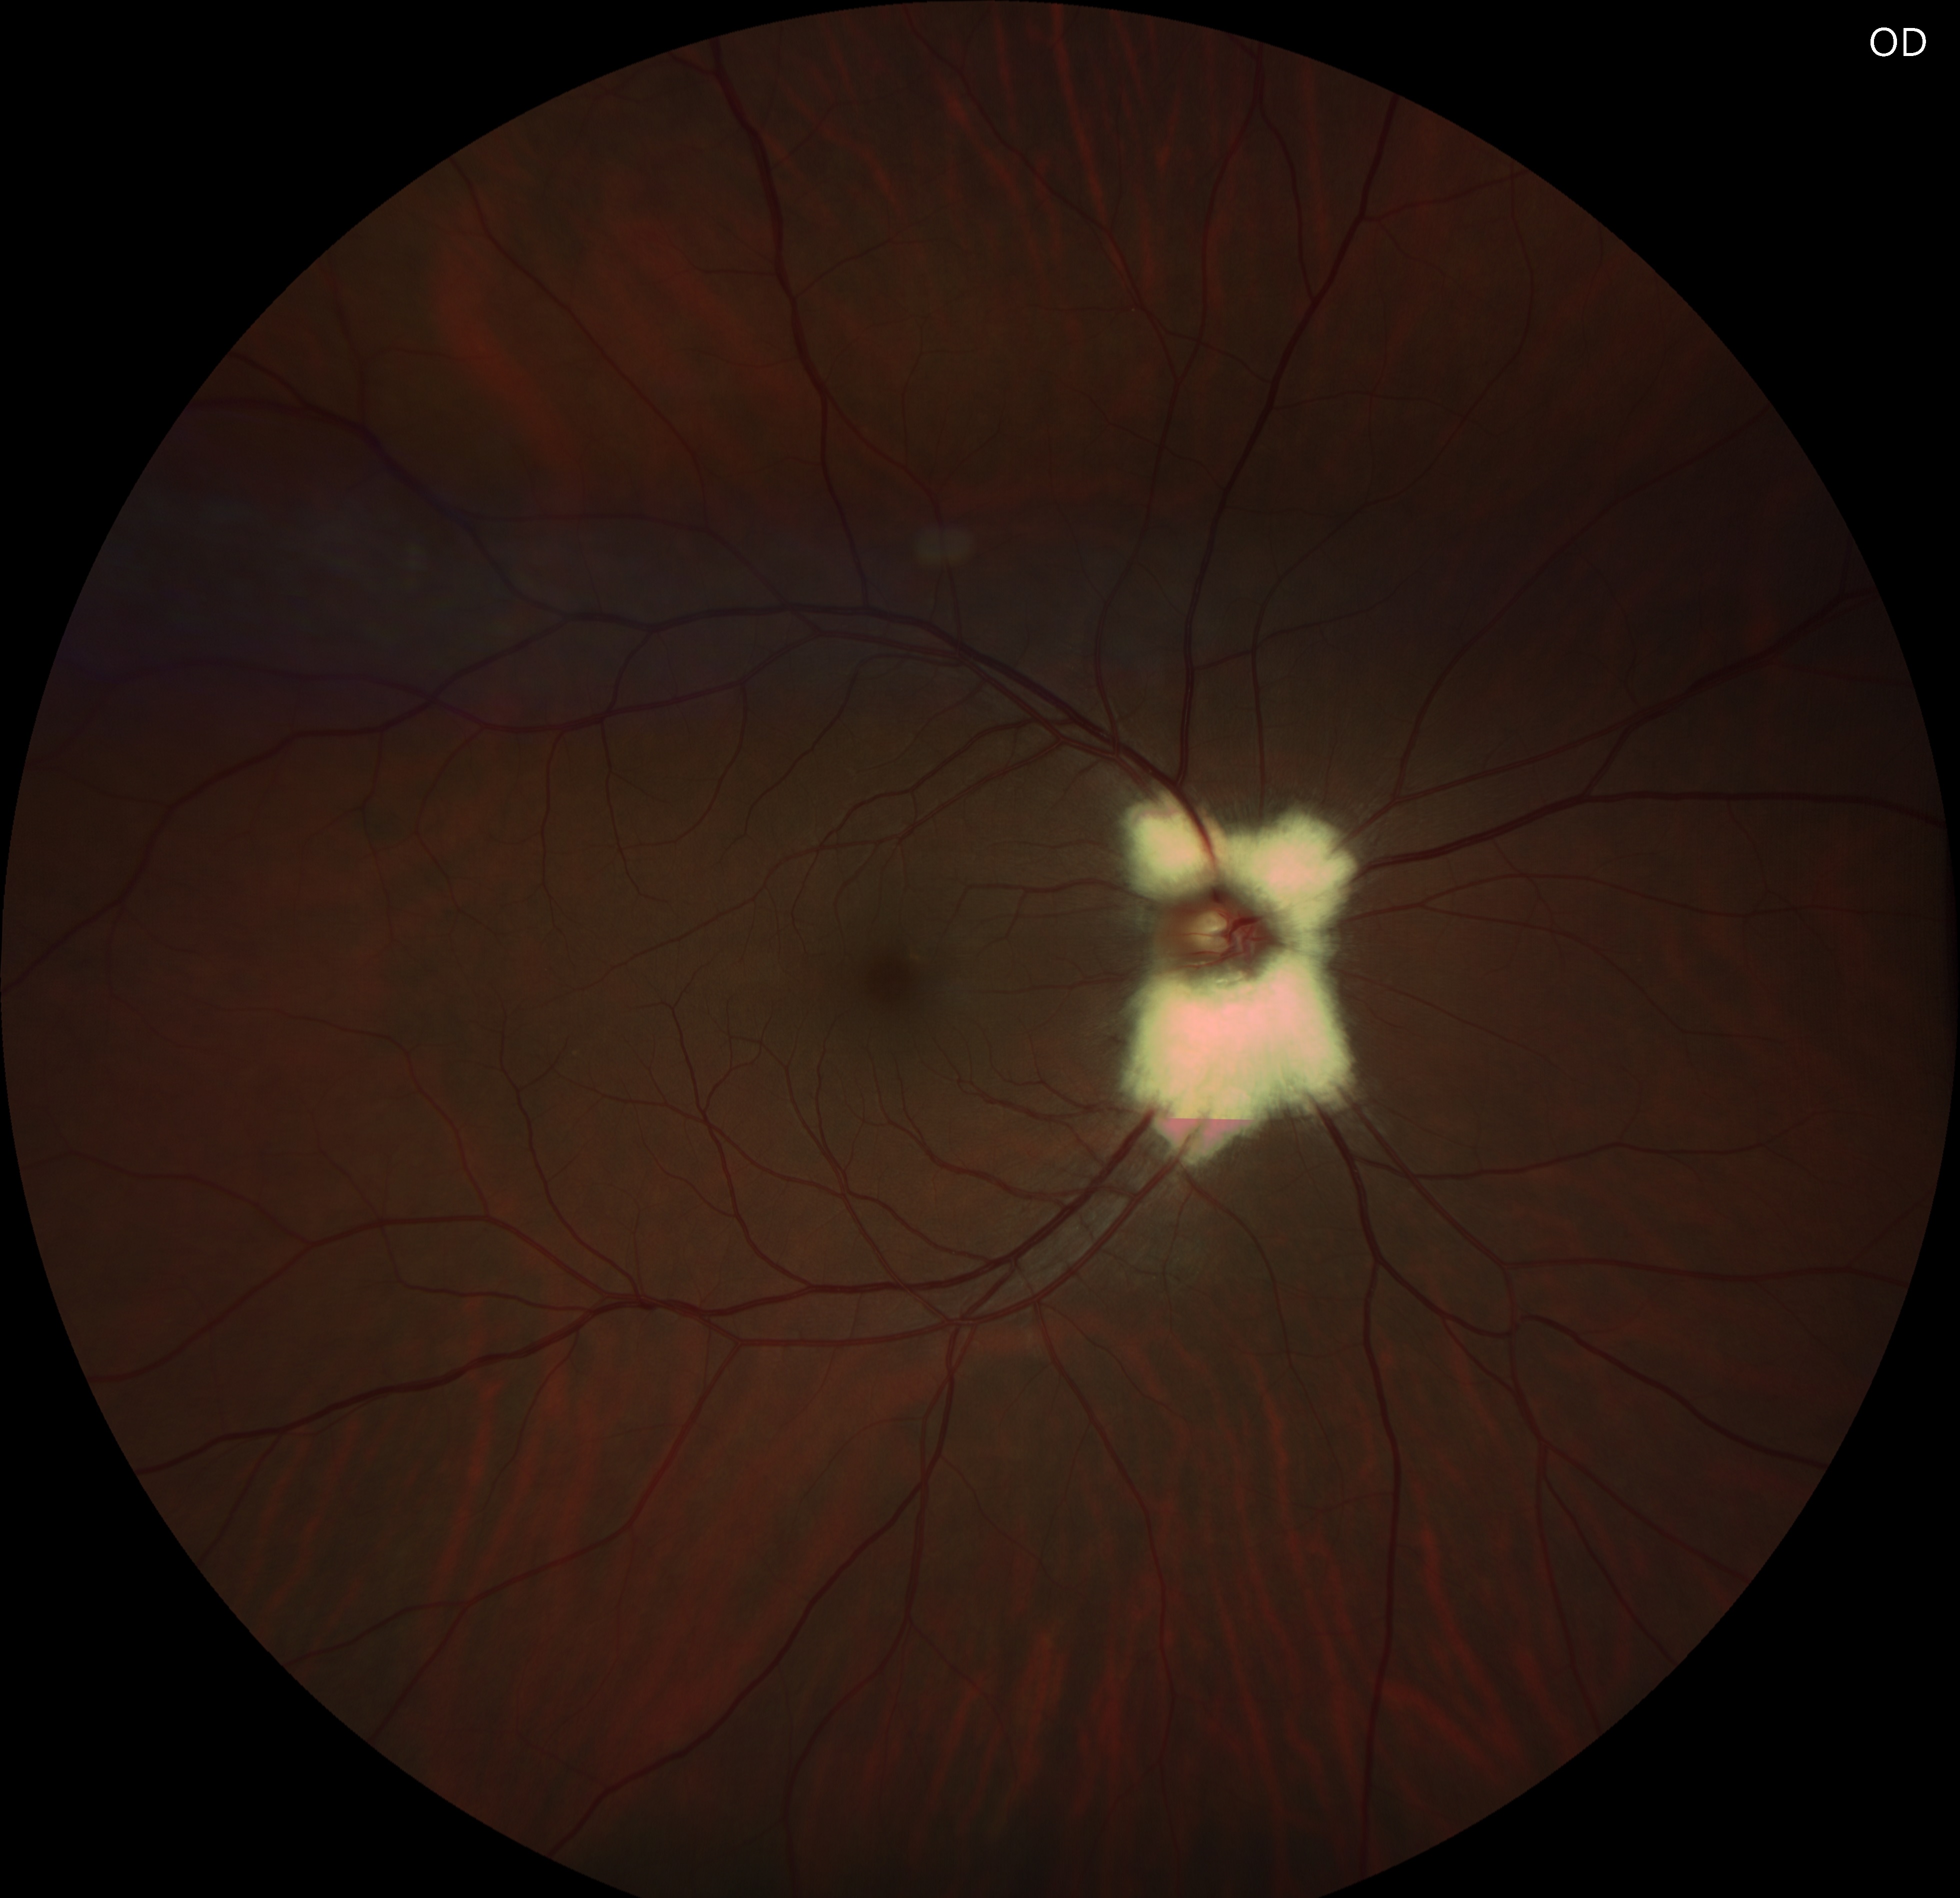

Fundus examination revealed a peripapillary, white-gray, striated patch with feathered borders, approximately one disc diameter in the right eye and half a disc diameter in the left eye.

Optical coherence tomography scans through these lesions demonstrated a thickened and hyperreflective retinal nerve fiber layer.

Myelinated retinal nerve fibers are a rare, benign finding in the eye. Normally, retinal nerve fibers are unmyelinated, but in MRNF, myelin extends into the retina, appearing as white or gray striated patches near the optic disc. They are usually discovered incidentally during routine eye exams and are typically asymptomatic. While vision is often normal, MRNF can sometimes be associated with high myopia or amblyopia. Optical coherence tomography (OCT) shows a thickened, hyperreflective retinal nerve fiber layer corresponding to the lesion. No treatment is needed, but regular monitoring is recommended to rule out other retinal pathologies.